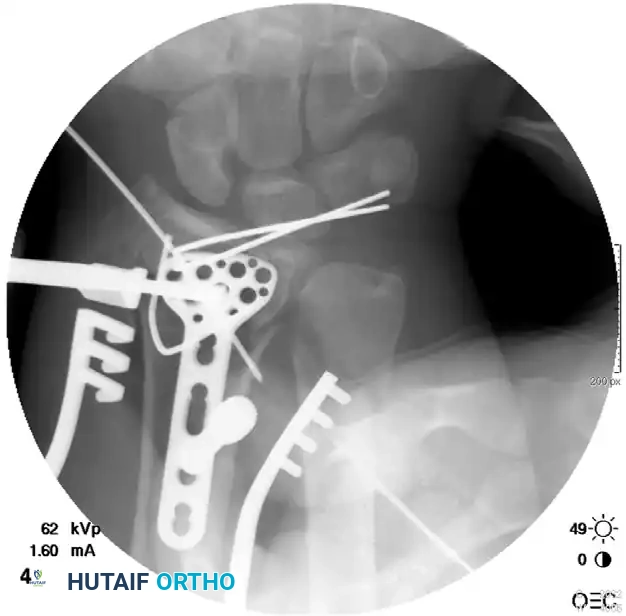

5. Distal Fixation:

Secure the plate to the long finger metacarpal shaft using three bicortical 3.5-mm screws.

6. Distraction and Proximal Fixation:

Under fluoroscopic guidance, apply longitudinal distal traction to the fingers to obtain normal radial length and restore the radiocarpal joint space via ligamentotaxis. With the hand held in approximately 60 degrees of supination, secure the plate to the proximal radius with a bone clamp. Confirm that full rotation of the forearm is possible without impingement. Once confirmed, secure the plate to the radial shaft with three bicortical 3.5-mm screws.

7. Adjunctive Fixation and Grafting:

* Reduce and fix any large diaphyseal fragments to the shaft with interfragmentary lag screws if possible.

* Through the middle incision, elevate the depressed lunate fossa.

* Insert a 3.5-mm screw through the plate and under the elevated lunate fossa to serve as a subchondral buttress.

* Percutaneously pin other intra-articular fragments using Kirschner wires to stabilize the articular surface.

* Place bone graft (autograft, allograft, or synthetic substitute) into the metaphyseal voids through the middle incision.

Radiographic Progression of Distraction Plating

The following sequence demonstrates a highly comminuted distal radius fracture successfully managed with a dorsal distraction plate:

Initial Injury Radiographs:

Postoperative Fixation with Distraction Plate:

Associated Surgical & Radiographic Imaging